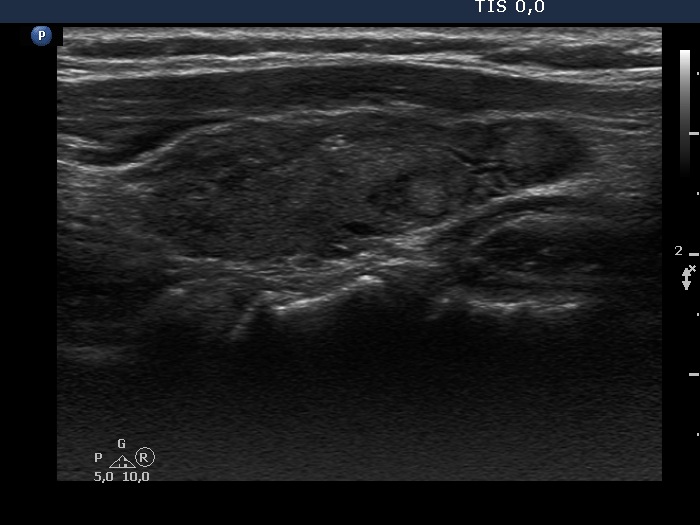

Consecutive patients with Hashimoto's thyroiditis - Case 10. (ultrasonographic picture 6)

Left lobe, longitudinal scan. This lobe is minimally hypoechogenic. There are two discrete areas which are divided by capsule from the non-lesional part. The echo pattern of the discrete lesions is identical to the non-lesional part of the lobe.